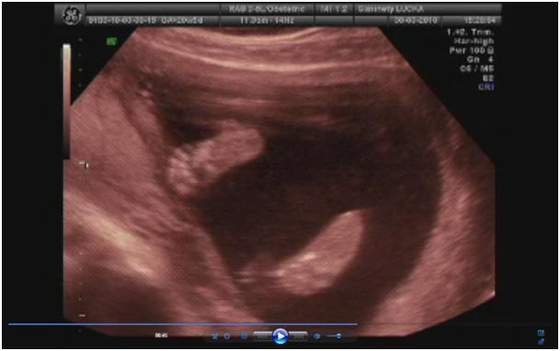

no niby 3500 ale to raczej mało możliwe (sam przyznał) skoro 2 tygodnie temu miała 2700

ale usg było jakie było i kazał się tym nie sugerować -ważne że urosła